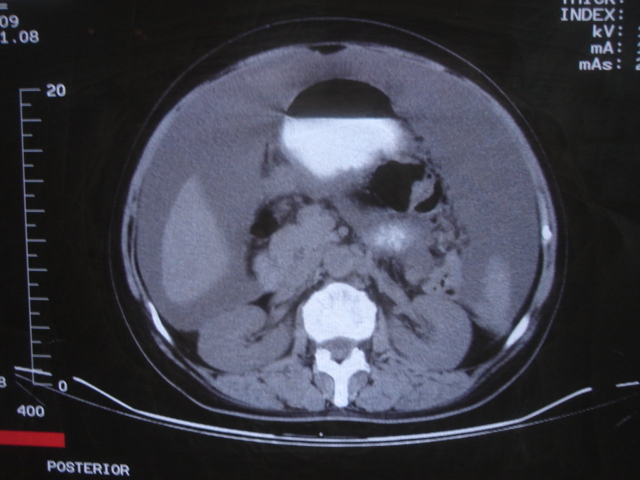

患者 女 52 腹部大量腹水。大家帮忙看看胃窦部有问题吗?

b超显示腹部、盆腔未见异常;化验室检查afp cea 正常,ca125 升高 347.4。

腹部大量腹水。胃窦部胃壁增厚,轮廓不规则!

1)不排除胃癌可能;建议行胃镜检查。2)大量腹水。

网膜不干净,可能为癌性腹膜炎。

胃窦部胃壁限局性增厚,不排外腹膜病变的影响。

胃窦癌腹膜转移可能。

腹部大量腹水。胃窦部胃壁增厚,轮廓不规则,胃癌待除外,建议胃镜检查。